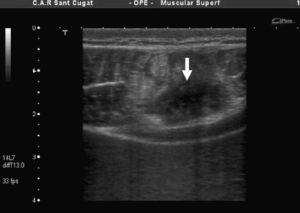

En el tenis se describe una asimetría de ambos RA2, con diferencias significativas en el diámetro anteroposterior del lado dominante (21,2mm±1,93) respecto al no dominante (28,2±1,93). En jugadores atacantes de voleibol se observa el mismo fenómeno. La figura 4 corresponde a un jugador sano perteneciente a la selección nacional donde se da la misma circunstancia.

Figura 4. Asimetría muscular de recto abdominal en un jugador profesional sano: 25mm en lado izquierdo no dominante, 20mm en el derecho.